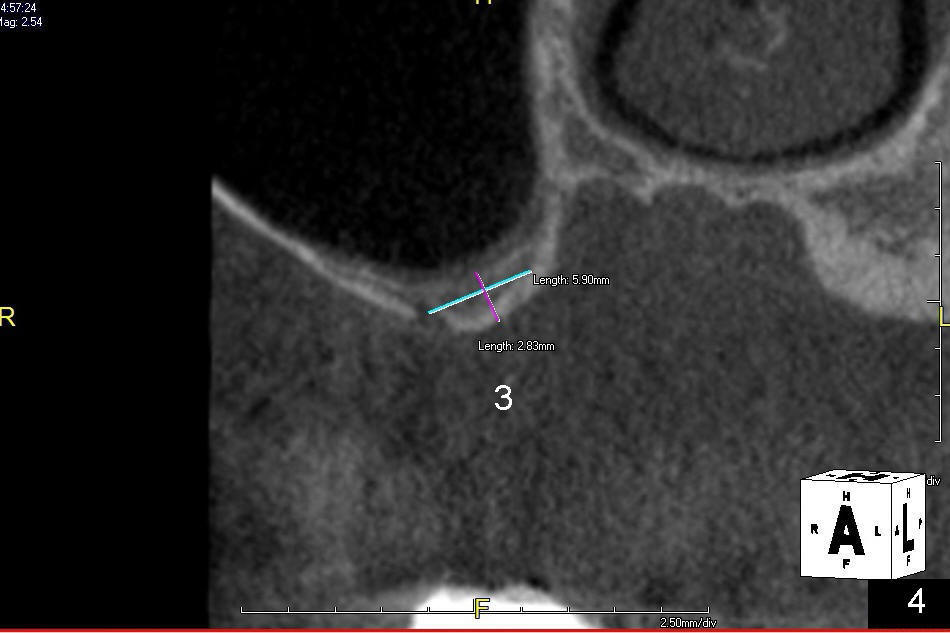

A 56-year-old lady lives out of state. She requests implant treatment for the upper right quadrants. Implants were removed by her previous care provider due to pain and infection. The premolars (Fig.1: #4,5) are provisionalized with a mini-implant (*). CBCT scans (Fig.1,2 (sagittal sections); Fig.3-6 (coronal section) show limited bone height involving the sites of the teeth #2 (Fig.1,3), 3 (Fig.2,4) and 4 (Fig.1,5). The buccolingual width is narrow at the sites of the teeth #4 and 5 (Fig.5,6).